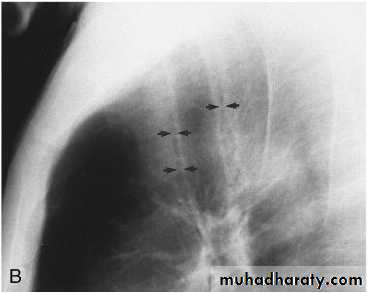

Miliary Tuberculosis. A cone-down view of a frontal radiograph demonstrates innumerable micronodular opacities characteristic of micronodular (miliary)

interstitial disease.

Transbronchial biopsy demonstrated caseating granulomas containing acid-fast bacilli.

Miliary TB

a frontal radiograph demonstrates innumerable micronodular opacities characteristic of micronodular (miliary) interstitial disease. Transbronchial biopsy demonstrated caseating granulomas containing acid-fast bacilli.